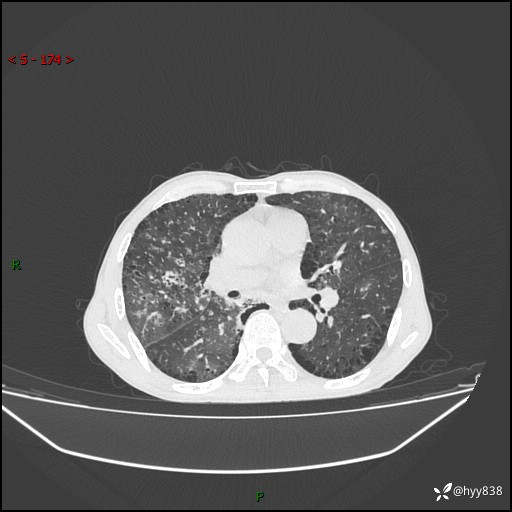

胸部CT平扫